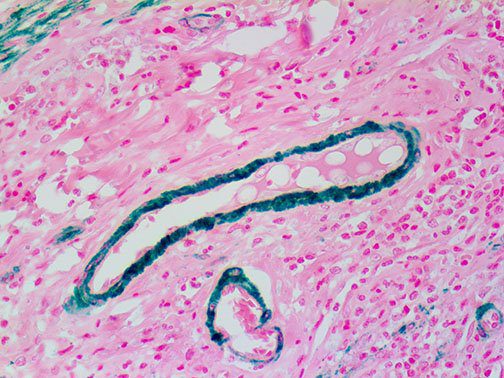

This activation induces inflammatory monocytes to highly express IL-6, starting a localized and then systemic cascade effect that results in hyperproduction of IL-6, which accelerates the inflammatory process. Because IL-6 also increases vascular permeability, excessive levels cause blood vessels to become very leaky. This, along with clotting factors released from vascular endothelial cells, stimulates the coagulation cascade, resulting in microthrombosis (tiny clots), which leads to ischemia and tissue death of the kidney, intestines, heart, liver, brain and extremities.